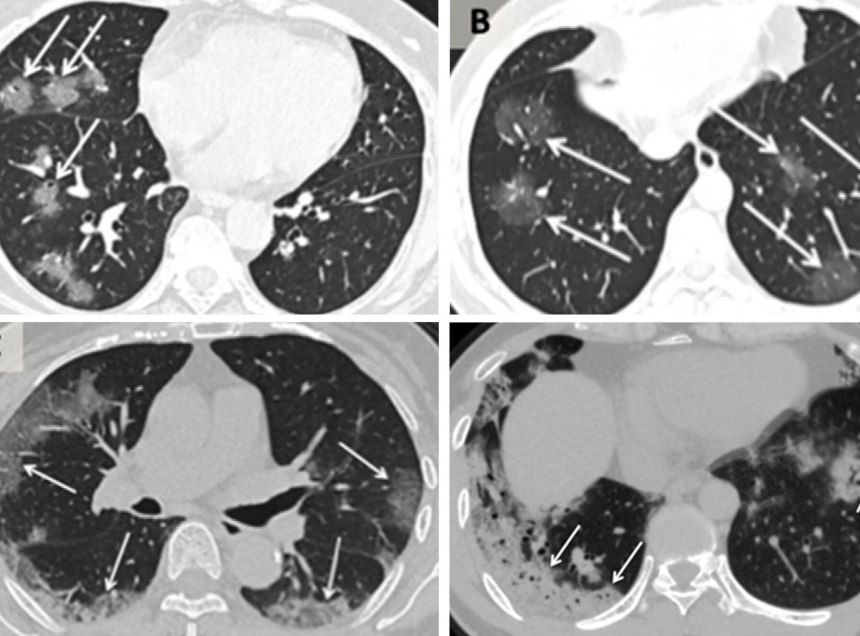

«За год картина изменилась. Нет связи между внешним проявлением симптомов и степенью поражения легких. Человек может быть с высокой температурой, отдышкой, плохо себя чувствовать — и поражено у него будет только 5-10% легких. А может придти с легким кашлем, а мы видим у него картину поражения до 50%. Но в целом — всегда учитывается совокупность всех клинических показаний», - рассказал Питер Туйнеза. Он отметил, что в его практики были пациенты, когда КТ показывало и 90 и 100-процентное поражение легочной ткани.

При лечении динамика восстановления легких заметна на КТ или ренгген-исследовании. «Скорость восстановления у всех разная, но динамика есть. Легкие восстанавливаются, не всегда полностью, но восстанавливаются», - сказал медик.